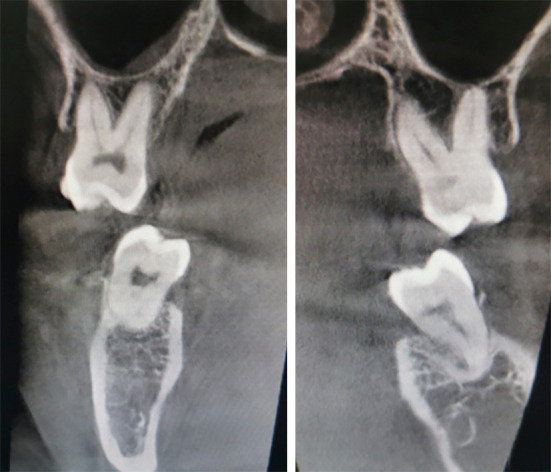

使用无托架的透明矫正器治疗双侧磨牙深覆咬合并颊交叉咬:一个病例描述。

Management of bilateral molar deep overbite with buccal crossbite using bracket-free clear aligners: a case description.